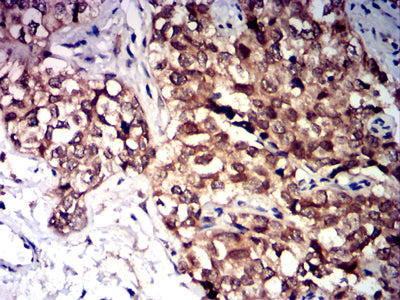

Immunohistochemical analysis of paraffin-embedded human bladder cancer tissues using CD47 mouse mAb with DAB staining.